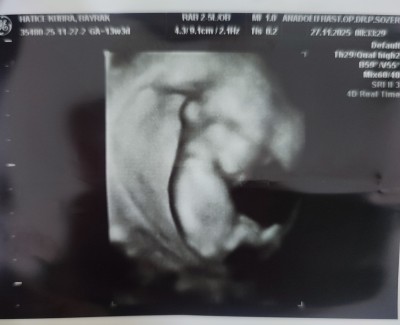

11 haftalık ve 13+5 haftalık ultrason görüntülerimiz doktor cinsiyette emin olamadi önce erkek sonra kız dedi ama sizin tahminleriniz neler?

Gebelik haftası 13+5

Bacak arasında uç cızgı var gıbı canm kıza benzettim bende

Kız hissettim

Kız sanki☺️